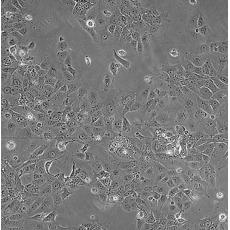

HCC827

產品名稱 HCC827

中文名稱 人非小細胞肺癌細胞

組織來源 肺腺癌;女性

細胞種屬 Homo sapiens, human

生長特性 adherent

培養基 RPMI-1640+10% FBS+1% P/S

形態特征 epithelial

傳代方法 1:3-1:6

細胞描述 This lung adenocarcinoma has an acquired mutation in the EGFR tyrosine kinase domain(E746-A750 deletion).